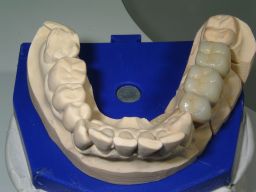

| Im Frontzahnbereich sind die weißen Kompositfüllungen natürlich das Mittel der Wahl. Auch kleine Füllungen, inbesondere in den vorderen, besonders sichtbaren, kleinen Backenzähnen, lassen sich mit Composite gut versorgen. Generell gilt: Je größer die Füllung, desto größer wird der Haltbarkeitsvorsprung für Amalgam. Die ästhetische und über Jahrzehnte haltbare Alternative zu großen Amalgamfüllungen sind deshalb nicht große Kunststofffüllungen, sondern keramisch verblendete Kronen, die problemlos auf die mit Amalgam sanierten Backenzähne zementiert werden können: | ||||||||||||||||||||||||||||||||||||||||||||||||||||||||||||||||||||||||

| Die Patientin wünschte eine dauerhafte, weiße Versorgung. | ||||||||||||||||||||||||||||||||||||||||||||||||||||||||||||||||||||||||